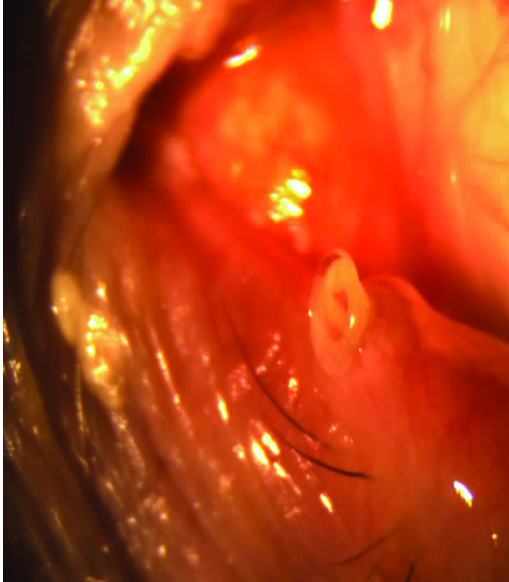

En mi experiencia y opinión personal, sostengo hace largo tiempo que el uso de los denominados tapones lagrimales de silicona pueden agravar los cuadros inmunológicos y/o inflamatorios presentes en el ojo seco, al fomentar los fenómenos inmunocompentes por fricción sobre la superfcie ocular (Figs. 22, 23, 24).

Figura 22: Borde del tapón lagrimal sobre la superficie conjuntival y acúmulos secretorios secundarios.

Figura 23: Borde del tapón deteriorado friccionando la superficie ocular. Secreción, congestión y edema conjuntival.

Figura 24: Contacto del tapón lagrimal en conjuntiva.

Sostuve y sostengo también, que esa fricción crónica puede estimular a los linfocitos conjuntivales y en pacientes susceptibles desencadenar fenómenos de tipo linfoides.

Ambas presunciones han sido recientemente informadas (REF).